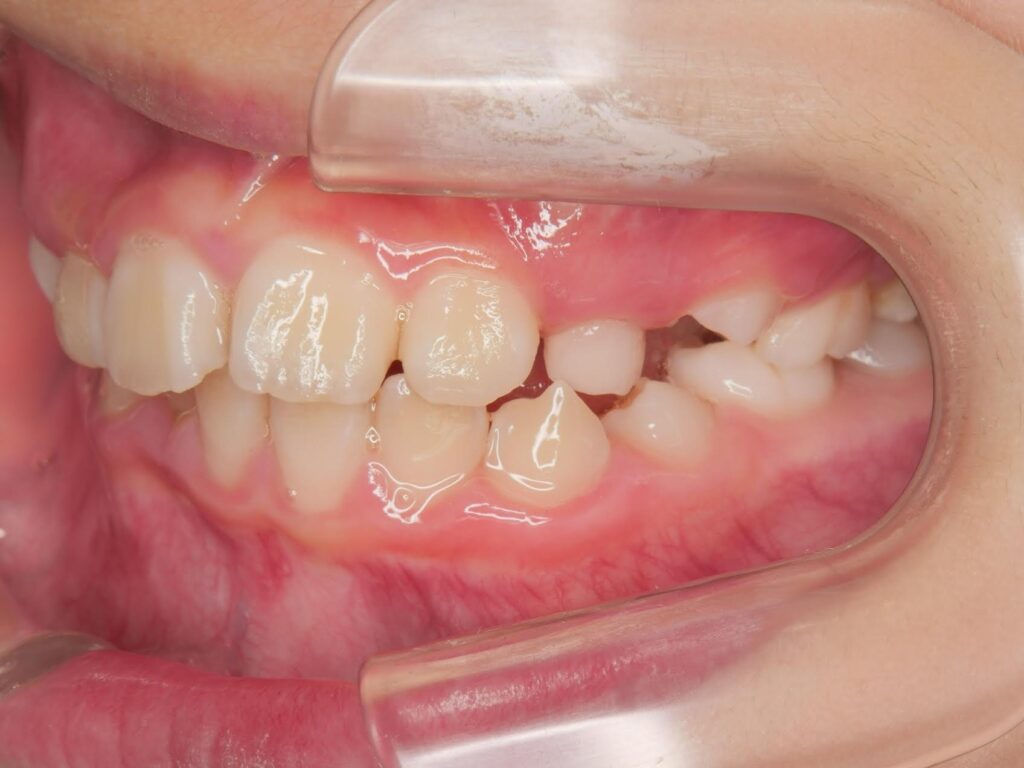

初診時の画像診断

上下の歯並びにガタガタがあります。

左の前から3番目の歯の噛み合わせが上下反対に噛んでいます。

その影響で上下の前歯の真ん中のラインが右にずれています。

1つ目は、上下ともに少しガタガタがあること。

2つ目は、噛んだ時に上下の前歯の真ん中のラインが少しズレていること。

3つ目は、左側の一部だけ上下が逆に噛んでいる(交叉咬合)ところがあることです。